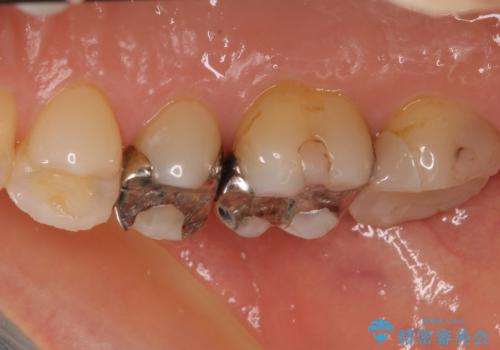

- 奥歯の銀歯をすべてゴールドにすることを希望された患者様です。

セラミックインレーによる補綴治療も提案しましたが、ご自身で強い咬合力を認識しており、歯にもインレーにもダメージの少ないゴールドインレーにて処置することとしました。